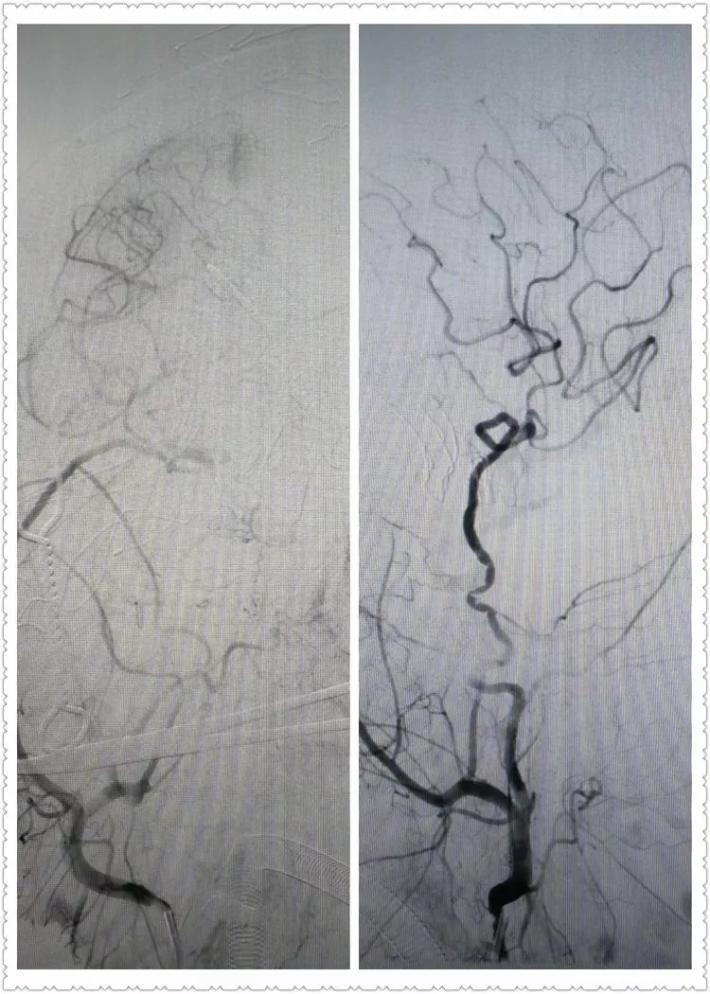

R-ICA正位:颈内动脉床突上段局部膨隆

R-ICA斜位:可见床突上段前壁一蘑菇状囊性突起,结合cT出血提示BBA,与家属沟通后选择介入治疗,我们拟采用Willis覆膜支架局部血管成形术!

释放支架后见BBA显影变浅,仅后半部分晚期显影,脉前A显影好,再次后扩。

二次后扩后颈内动脉造影见BBA逆向充盈部分显影,晚期仍有造影剂滞留,如远端再次叠套一支架必会累及脉前A,2周后复查DsA吧,希望BBA不破而且血栓自愈。

蒙片看支架释放成形很好,远端由于脉前A的原因覆盖的较短,故而有少量逆向渗漏,但是蒙片看造影剂晚期滞留明显,与家属沟通后终止手术! 2周后切线位DsA造影可看到造影剂充盈BBA,造影剂与支架间形成一充盈平面,与术后DsA形态比较明显增大,而且M1有明显的痉挛。